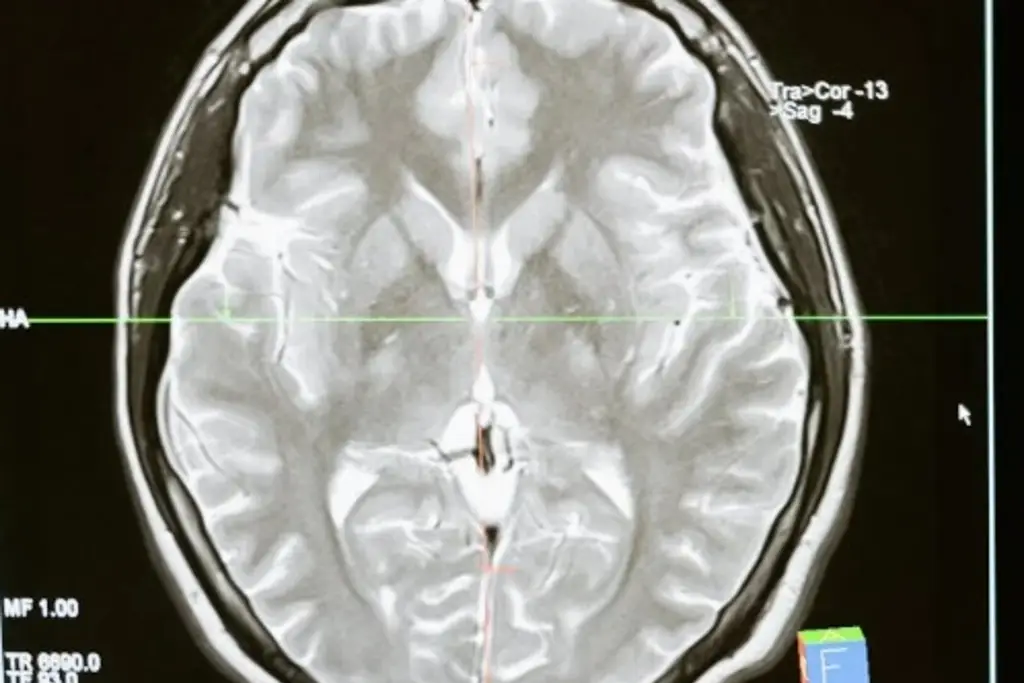

Un equipo de investigación de la Universidad de Ginebra (UNIGE) anunció este jueves que ha logrado crear células inmunitarias que reconocen y eliminan las pertenecientes al glioblastoma, un cáncer cerebral extremadamente agresivo y con muy bajas tasas de supervivencia.

El glioblastoma es un cáncer extremadamente resistente a la inmunoterapia, y con una tasa de supervivencia menor al 5 % cinco años después de su desarrollo.